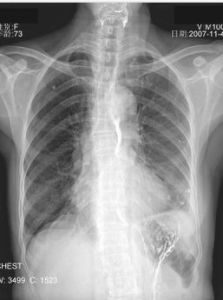

陳舊性肺結核,是指患者肺上出現的纖維化病變和鈣化的一種病症。放射科的診斷報告中提到的陳舊性肺結核,即指患者肺上出現的纖維化病變和鈣化。這樣的患者無潮熱、盜汗等結核中毒症狀,痰液內找不到結核桿菌。在隨後的胸部X線複查時,患者肺部的病變不出現任何變化。

放射科的診斷報告中提到的陳舊性肺結核,即指患者肺上出現的纖維化病變和鈣化。這樣的患者無潮熱、盜汗等結核中毒症狀,痰液內找不到結核桿菌。在隨後的胸部X線複查時,患者肺部的病變不出現任何變化。